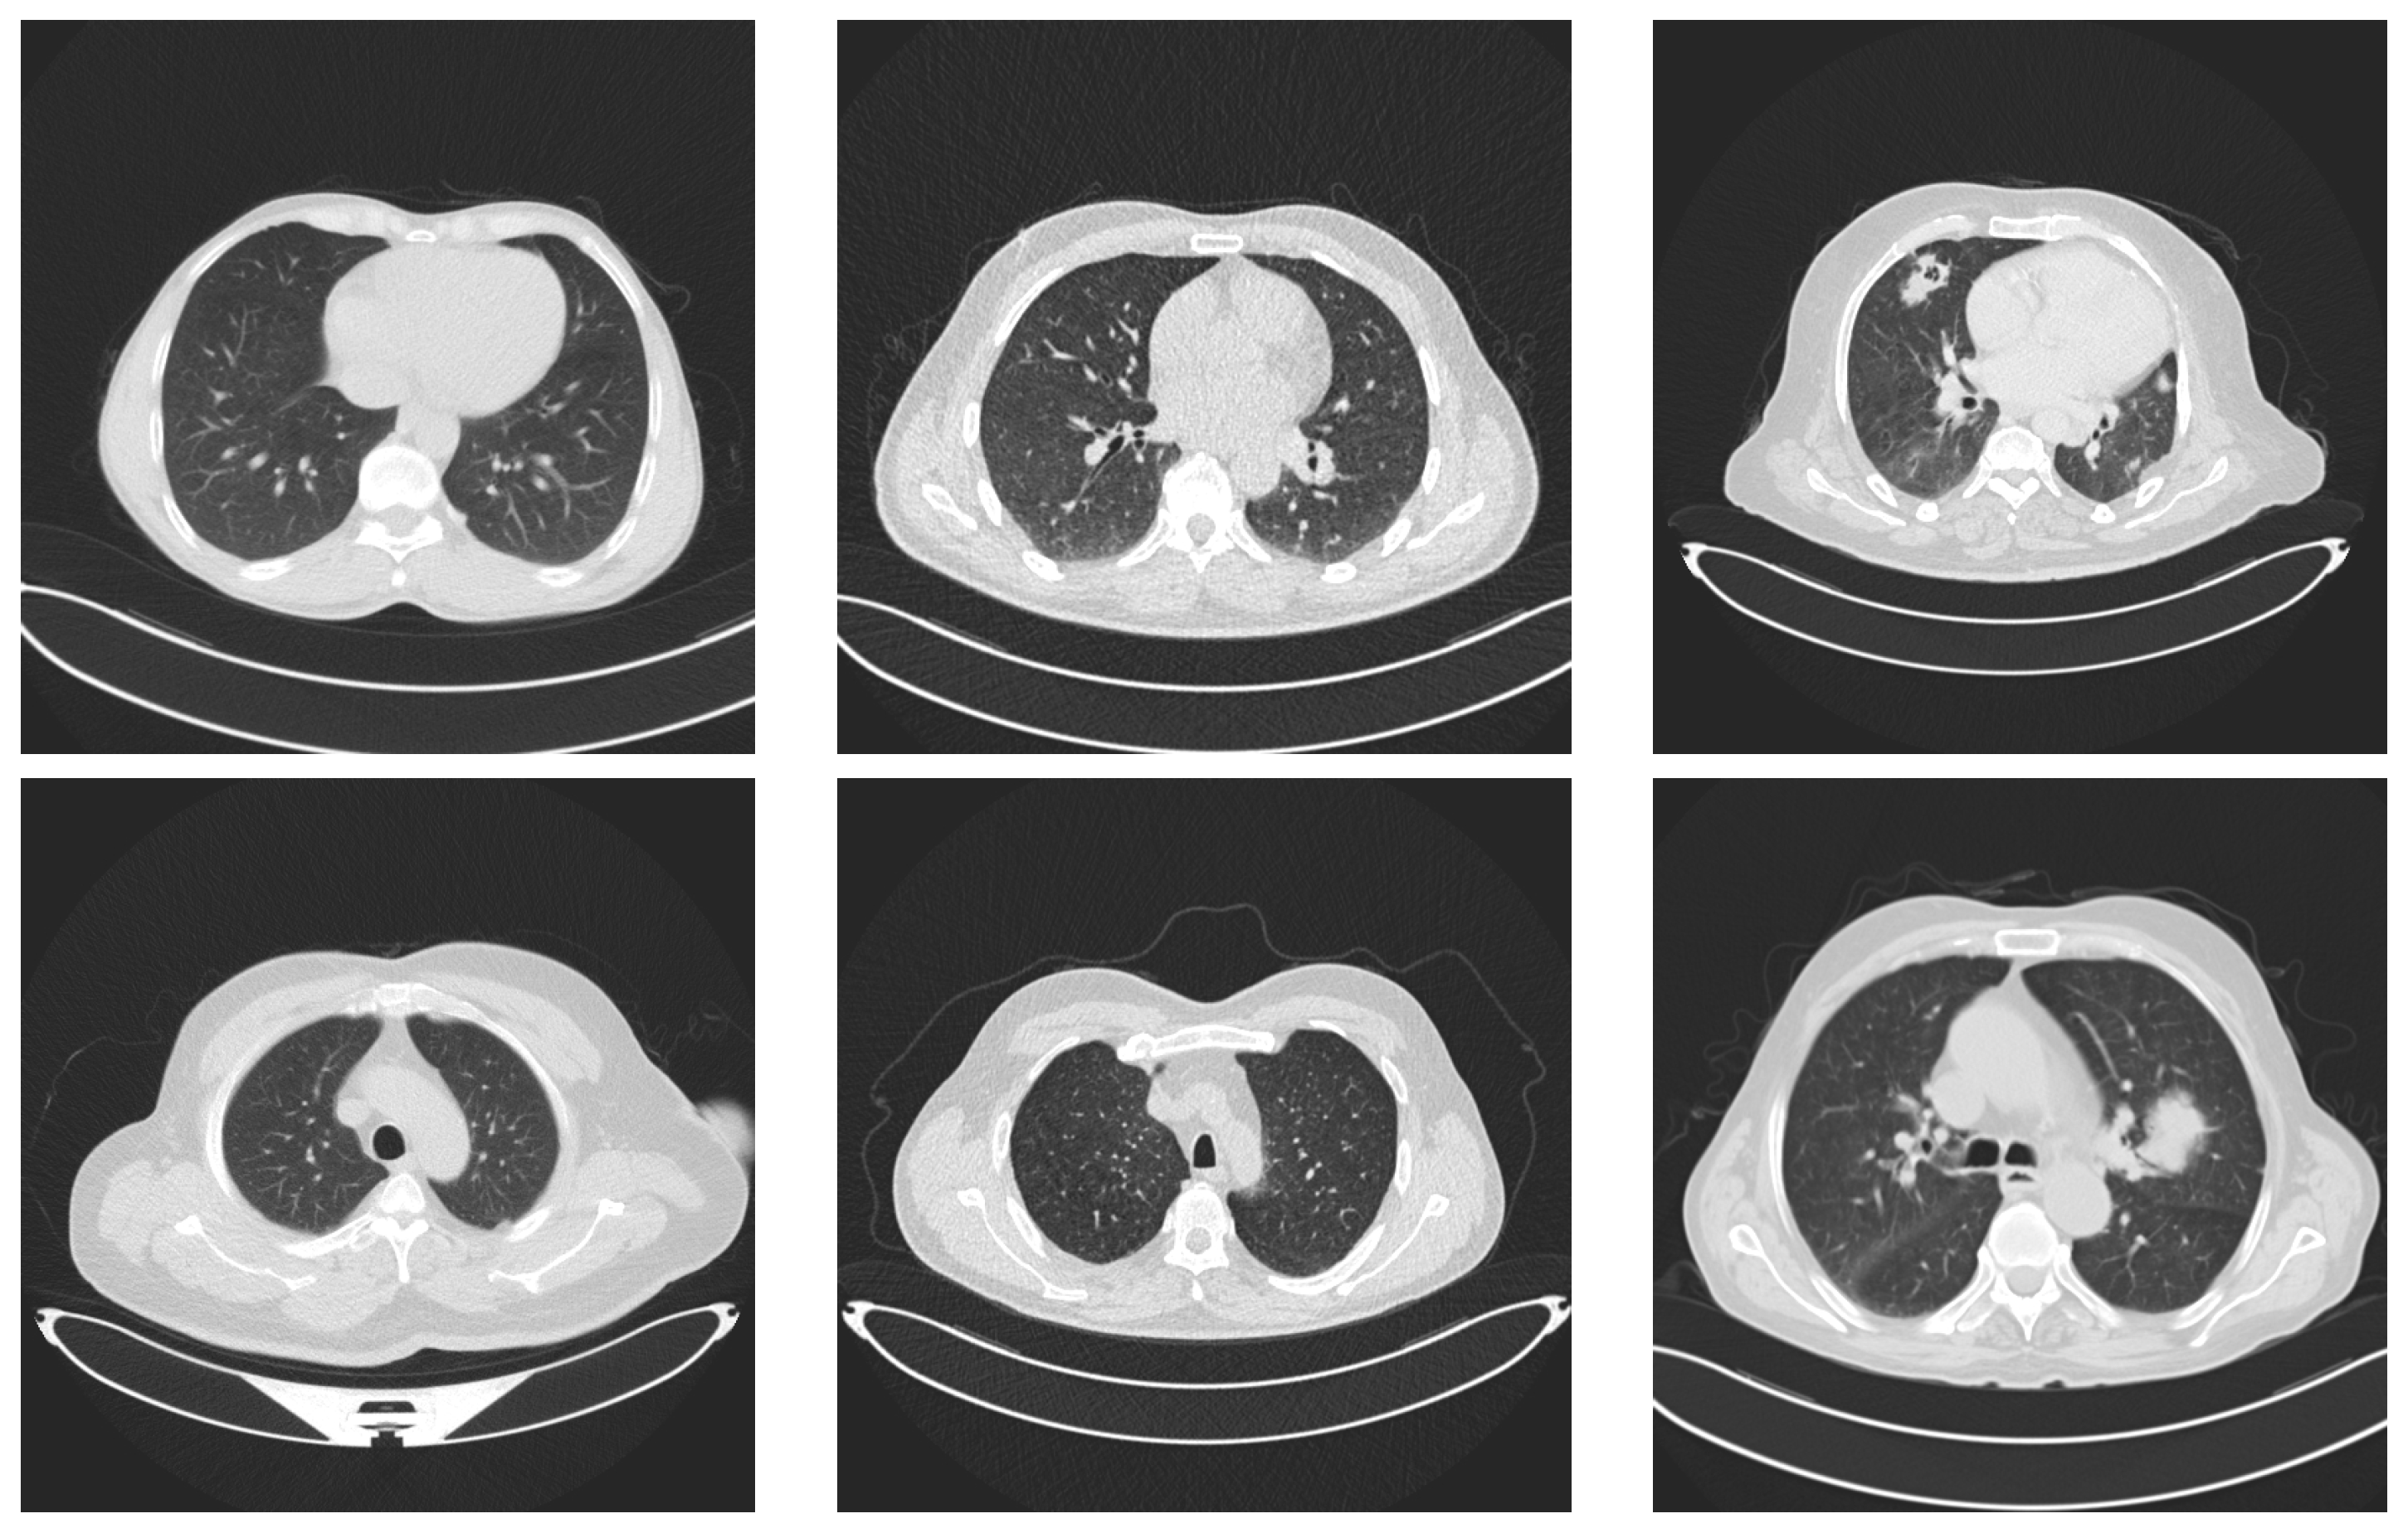

We selected a dataset from Kaggle [,] that includes CT scans of lung cancer and healthy lungs. The dataset has three classes: normal, benign, and malignant. Figure 2 depicts two examples of each class in the dataset.

Figure 2.

Examples of lung images. Images in the first column represent lungs with no tumors. The images in the middle column represent benign tumors and the last column contains two images with malignant tumors.